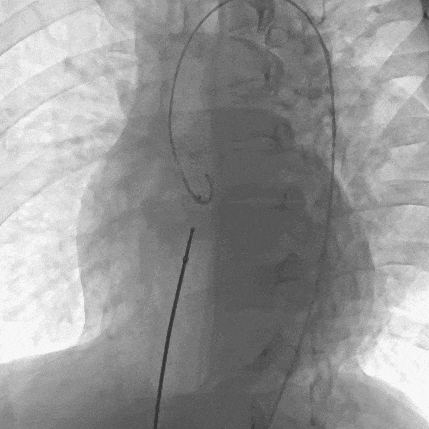

患者局麻后穿刺右股动脉及股静脉,经股动脉送入猪尾导管分别行左心室造影+主动脉根部行根部造影提示主动脉窦瘤破裂(无冠窦-右心房),持续大量左向右分流。明确病变位置后建立股动静脉轨道,经右侧股静脉送入输送鞘并送入先健12/14mm PDA封堵器。再次造影无分流,超声提示窦瘤破裂封堵完好,基本无残余分流,主动脉瓣未受影响。

再次主动脉根部造影显示封堵良好,残余分流不明显

术后左心室造影评价有无合并室间隔缺损